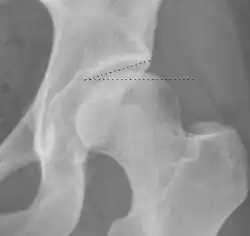

Crossing ratio Percentage of acetabular walls crossing. Normal acetabulum is oriented in anteversion. Its value ranges from 15 to 20° in the equatorial plane of the acetabulum and decreases gradually towards the acetabular roof, where normal values range from 0 to 5°. Retroversion of the upper part of the acetabulum has been related with pincer type impingement. In radiography the presence of a "crossover sign" is produced when the posterior wall of the acetabulum crosses the anterior wall before reaching the acetabular roof. It is a sign of acetabular retroversion and it has been linked with overcoverage and pincer impingement. Nevertheless, this sign has been described in 6% of the normal population. Therefore, more important than its presence is the percentage of crossing. <20%

• Higher is significant crossing

Tönnis angle Slope of the sourcil (the sclerotic weight-bearing portion of the acetabulum) 0 to 10°

• >10° is a risk factor for instability

• <0° is a risk factor for pincer impingement